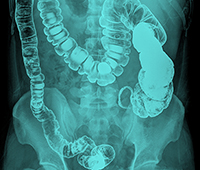

Definition

Acid reflux disease - also commonly known as Gastro-esophageal reflux disease (GERD) is condition in which acid from the stomach regurgitates or moves up into the esophagus (gullet).